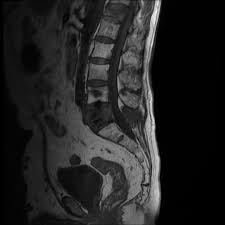

Https Onlinelibrary Wiley Com Doi Pdf 10 1002 Pros 2990250305

Https Onlinelibrary Wiley Com Doi Pdf 10 1002 Pros 2990250305 from